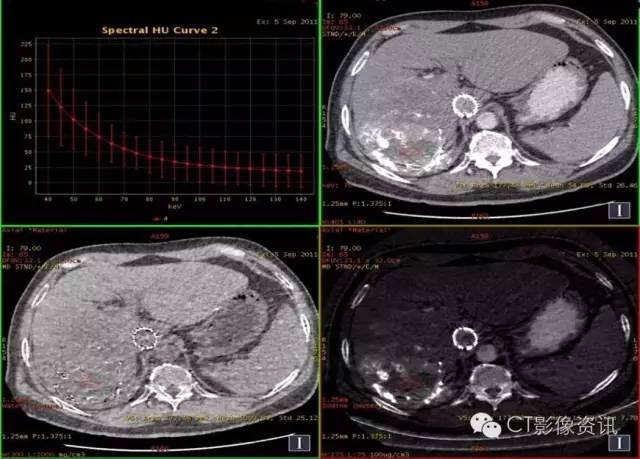

病史资料 男性,56岁,肝癌栓塞术后复查。

扫描参数 模式:GSI-22 375mA@0.7sec/rot@DC40mm@SFOV Body Large 螺距:0.984:1 平扫+增强扫描

平扫:碘9.03,水1018.90

动脉期:碘8.56,水1016.22

静脉期:碘8.25,水1016.37

缩小ROI后放在病灶碘油未沉积区比较如下:

平扫:碘2.05,水1001.88

动脉期:碘1.66,水1009.80

结论:此例平扫、增强多期碘基物质定量无显著差异。栓塞治疗效果较好。

临床优势 肝癌栓塞后,因碘油和术后炎性反应的影响,短期内难以评估手术效果。通过能谱成像GSI分析,比较增强后碘含量与平扫时碘含量(有时可用水含量)的变化及变化趋势,来判断肝癌病灶是否还有强化,评估栓塞治疗的疗效和预后,并可指导临床进一步治疗。